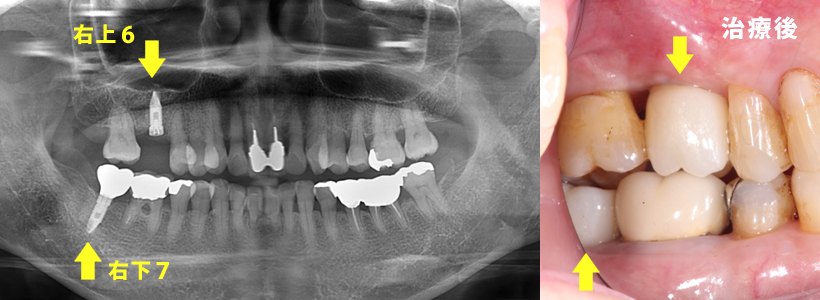

サイナスリフトによってかみ合わせが可能になるインプラント治療

エムドゲイン(歯周組織再生療法)と、CGF(あごの骨量を補う治療)を使用

<治療前>

右上6と右下7が駄目になっています

<CT画像での経過>

右上6と右下7にインプラントが埋入され咬み合わせができる状態。

義歯を応用したインプラント治療

<治療期間>

約1年3カ月